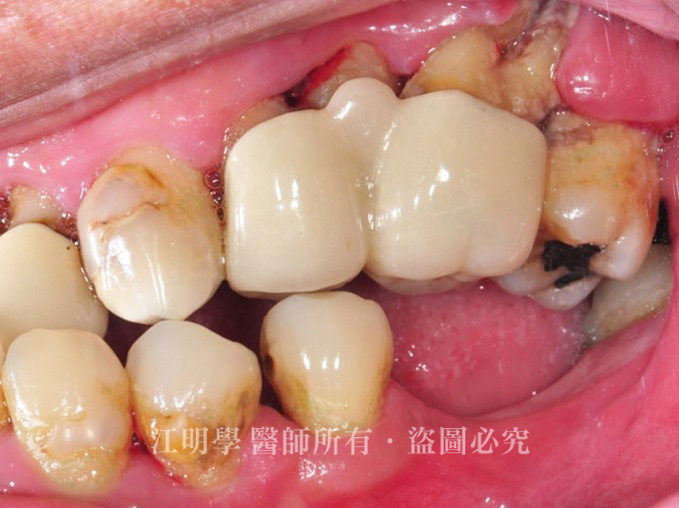

細菌隨口水滲入假牙內,造成二度蛀牙,需拆除舊的固定式假牙,重新評估齒質條件並擬定後續治療計畫。

治療前:牙肉因剌激而萎縮,假牙逐漸脫落,且因清潔不易,口腔常常伴隨嚴重異味。